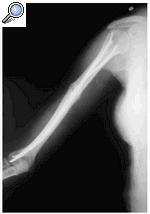

Los métodos incruentos no están exentos de inconvenientes, especialmente de tipo funcional y, por otra parte, no pueden aplicarse en determinadas circunstancias en las que exista alguna complicación de la fractura o que el paciente presente alguna patología asociada, por lo que algunas fracturas del húmero tienen una indicación de tratamiento quirúrgico.7 Una de las indicaciones es la fractura transversal del tercio medio del húmero puesto que suele evolucionar hacia una seudoartrosis5,6,7,10,14,18,29,42,43,44,46,48 (Fig. 1).

Figura 1. Fractura transversal del tercio medial del húmero (Tipo A3 de la AO).